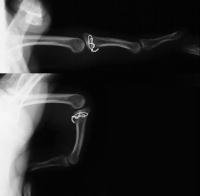

Xrays show an apparently healed PIP fracture dislocation with dorsal subluxation - but concentric tracking of the abnormal palmar articulation.

First impression was that the palmar fragment was probably big enough to take down and reinsert. However, comparison of films shortly after the fracture (above) and at two months (below) confirms the injury as a healed comminuted central impaction fracture with splay and hinging of the volar cortex.